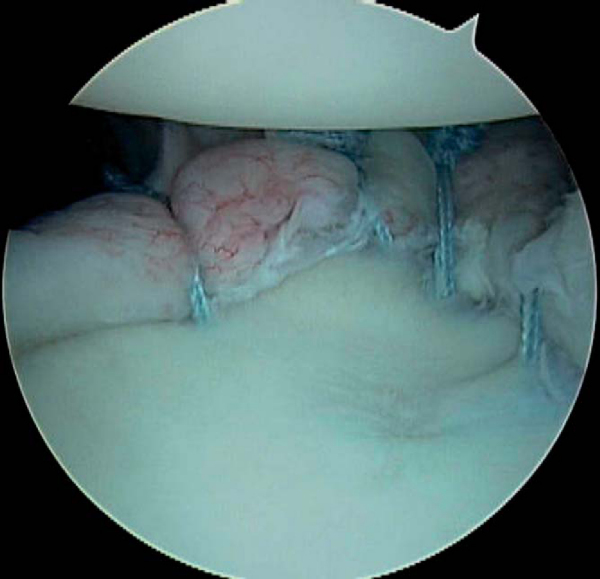

When the posterior labrum is detached, suture anchors are employed in performing the repair. The posterior labrum is visualized from both the posterior and anterior portals to appreciate the full extent of the tear (

Fig. 8-8

Figure 8-8 |